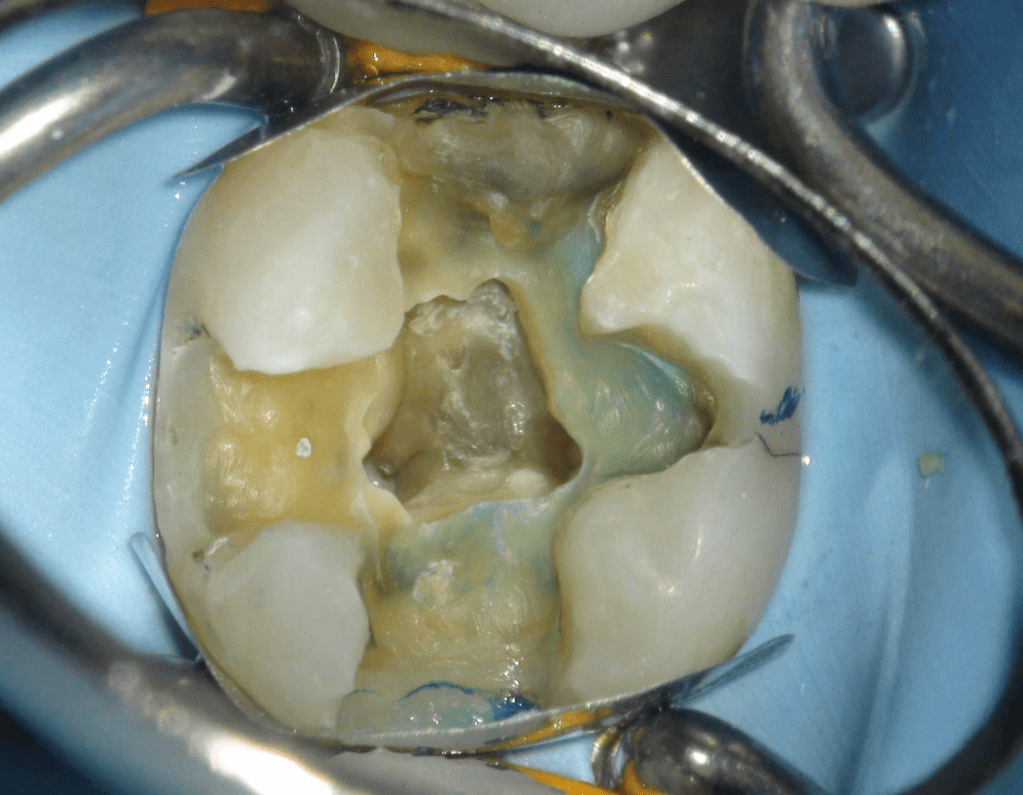

Pulpotomía biodentine + reco preendio